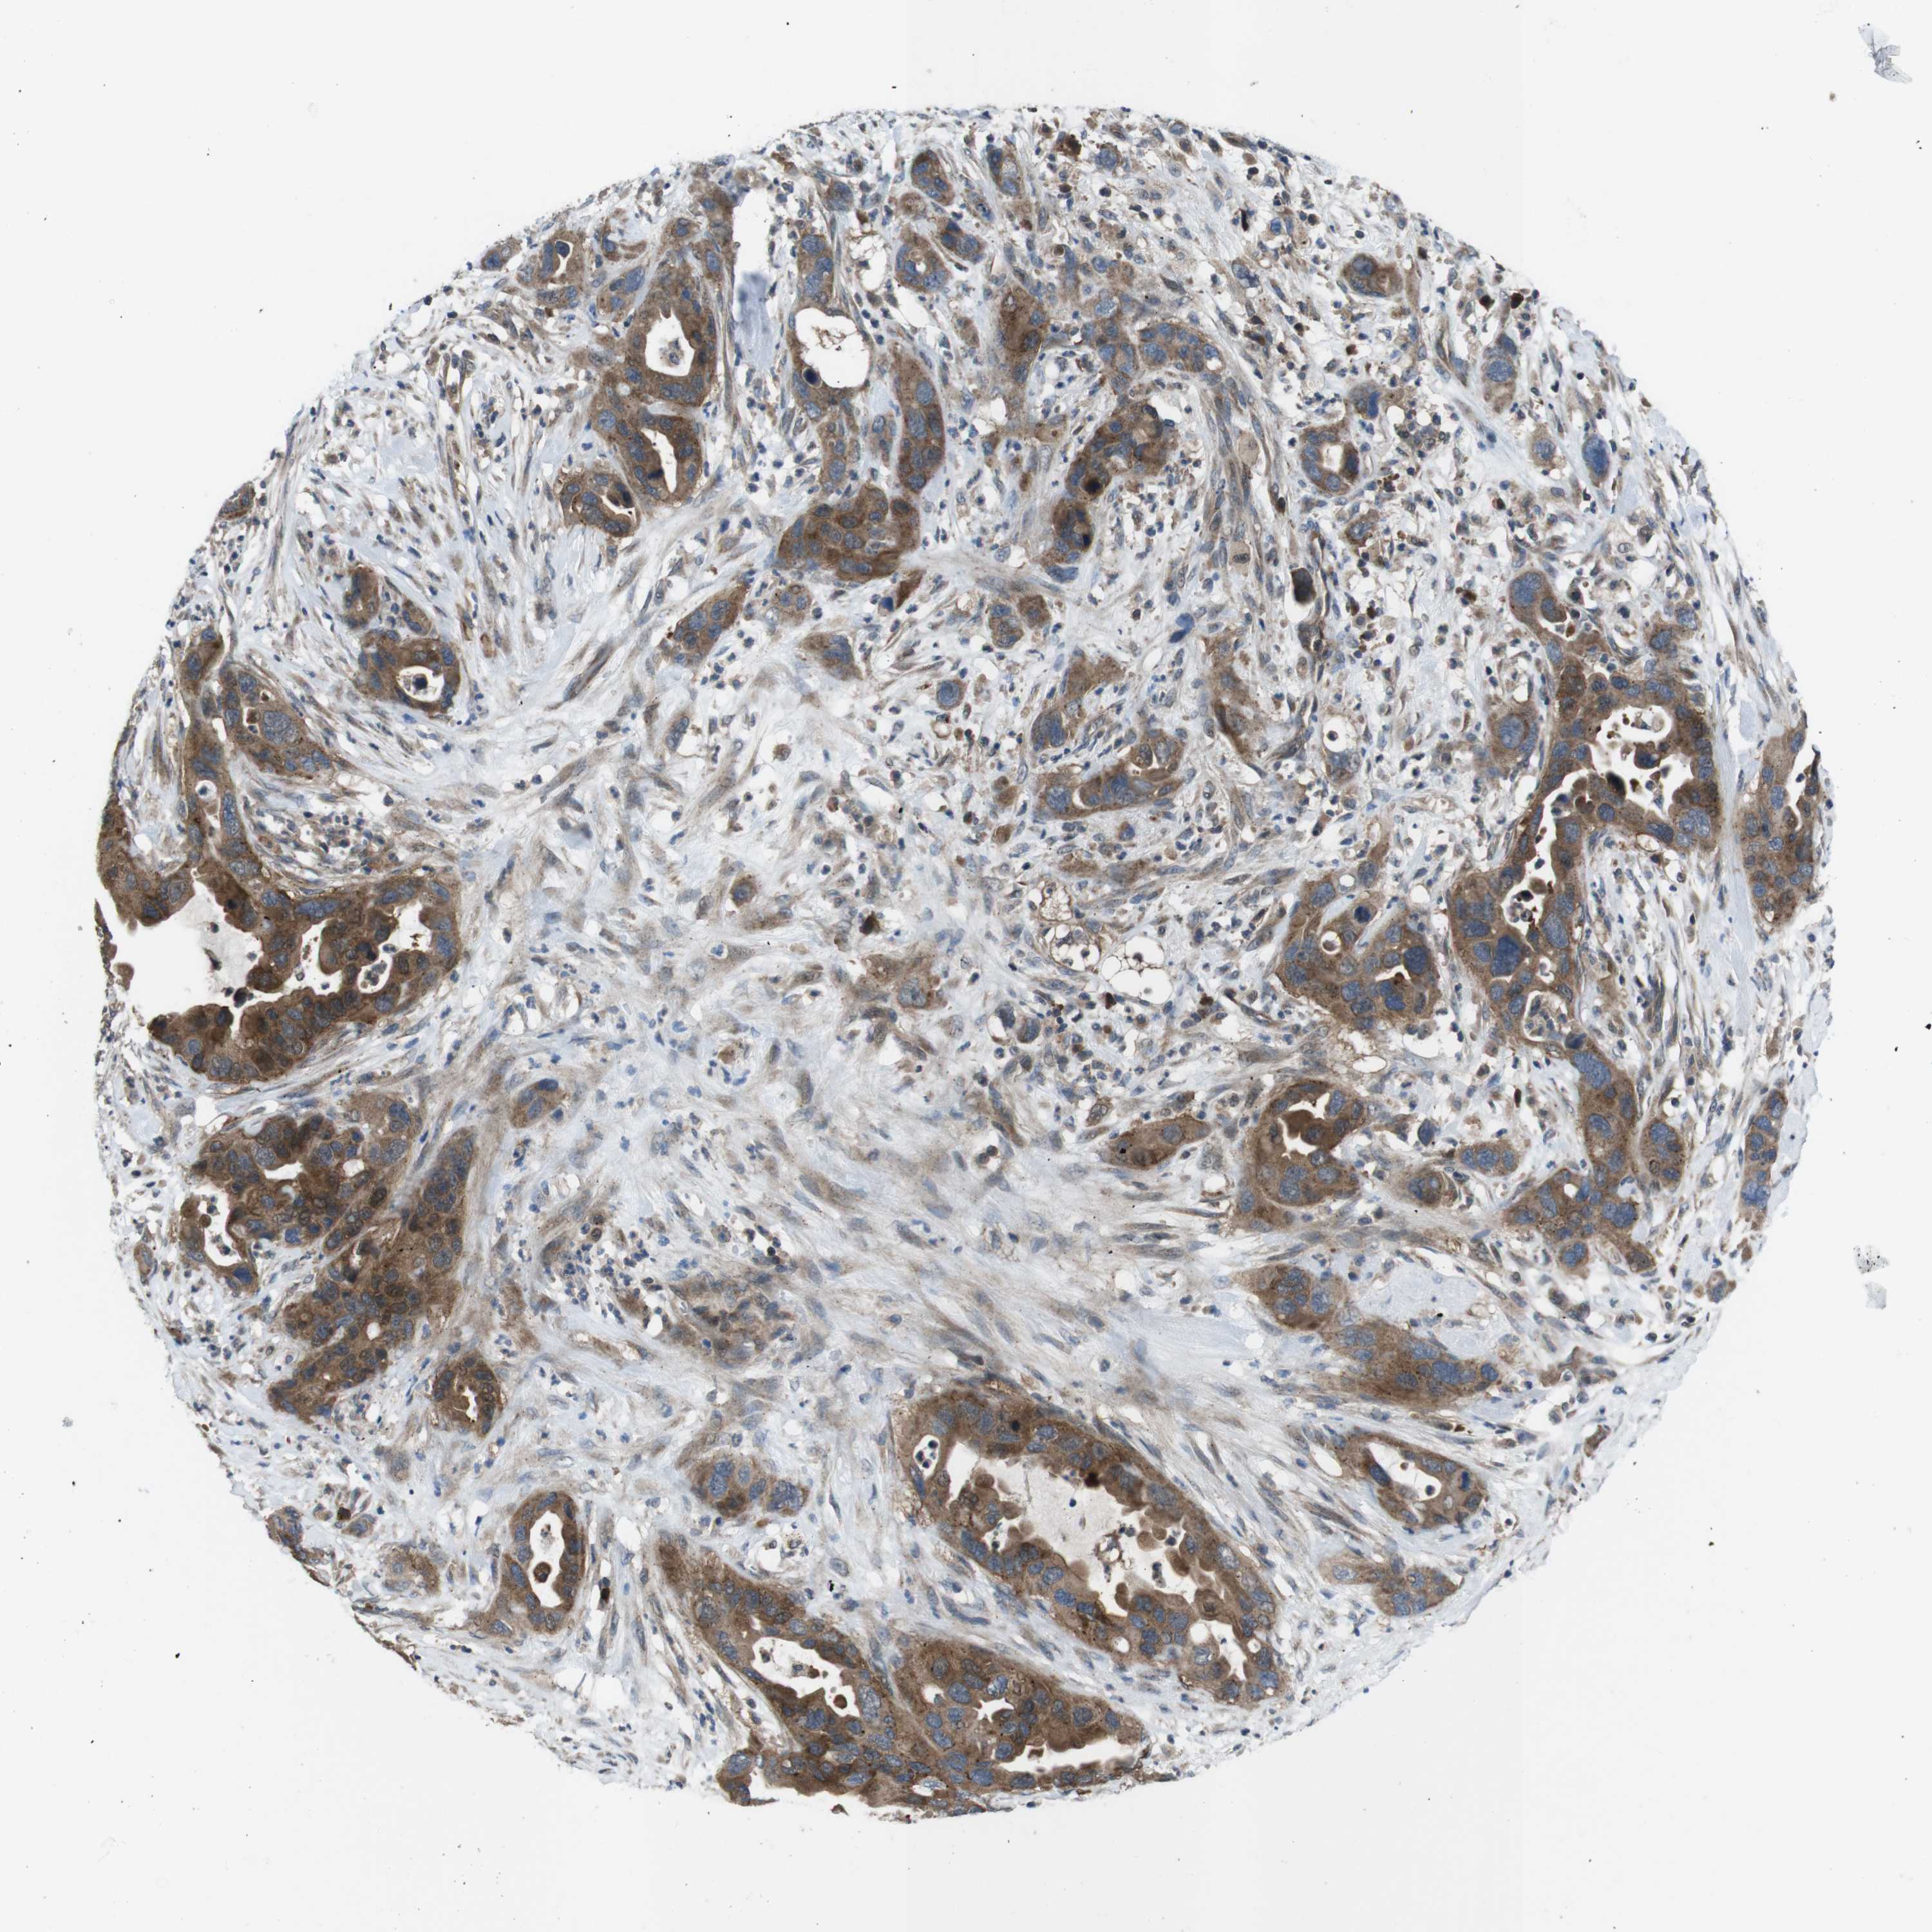

PANCREATIC CANCER - Protein expressioni

A mouse-over function shows sample information and annotation data. Click on an image to view it in a full screen mode. Samples can be filtered based on level of antibody staining by selecting one or several of the following categories: high, medium, low and not detected. The assay and annotation is described here.

Note that samples used for immunohistochemistry by the Human Protein Atlas do not correspond to samples in the TCGA dataset.

Antibody stainingi

Antibody staining in the annotated cell types in the current human tissue is reported as not detected, low, medium, or high, based on conventional immunohistochemistry profiling in selected tissues. This score is based on the combination of the staining intensity and fraction of stained cells.

Each image is clickable and will lead to virtual microscopy that enables deeper exploration of all samples and also displays staining intensity scores, fraction scores and subcellular localization as well as patient and tissue information for each sample.

Antibody HPA014697

Staining

High

Medium

Low

Not detected

Intensity

Strong

Moderate

Weak

Negative

Quantity

>75%

75%-25%

<25%

None

Location

Nuclear

Cytoplasmic/membranous

Cytoplasmic/membranous,nuclear

Adenocarcinoma, NOS